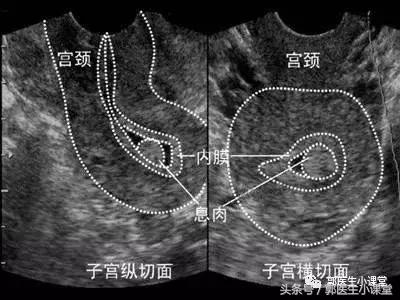

子宫内膜息肉在妇科算是比较常见的疾病,很多人可能平时没有任何不舒服的感觉,可能只是体检的时候做B超检查,结果B超报告就提示:子宫内膜增厚,不排除子宫内膜息肉可能,建议复查。

子宫内膜息肉是由子宫内膜局部过度增生所造成的,增生的内膜形成了一个或者多个凸向于子宫腔的肿物。这有点类似于宫颈息肉,只不过宫颈息肉是宫颈管部分的内膜组织增生,赘生物突出到了宫颈外而已。

子宫内膜息肉可以通过B超检查或者宫腔镜检查发现,一般采取手术治疗,不推荐药物治疗。